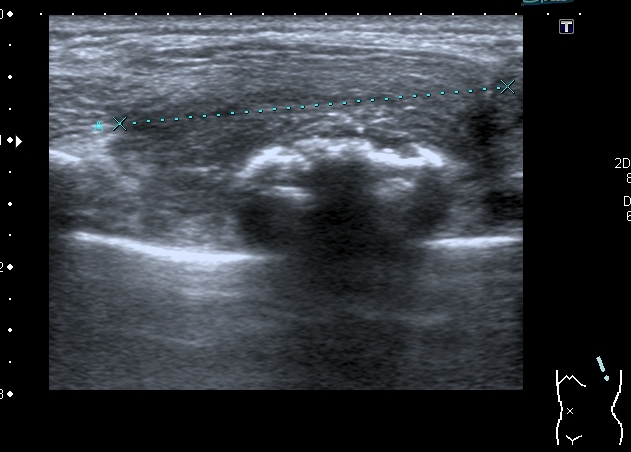

Деструкция корткального слоя 7-го ребра с ткаенвым компонетом, исходящим из кости. 7th rib destruction with solid mass

Поперечный скан. Transverse scan

После УЗИ - сделал рентген, изменения в ребре есть, но в глаза не бросаются

Diagnosis of Ewing's Sarcoma is suspected